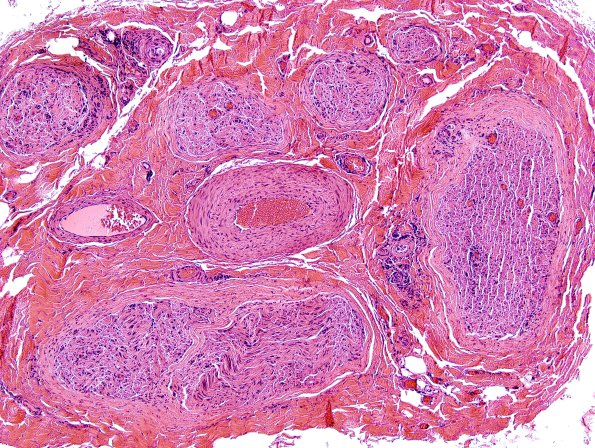

Washington University Experience | PERIPHERAL NEUROPATHY | 9B PERINEURITIS & PERINEURIAL PATHOLOGY | 5A1 Perineuritis (Case 5) H&E 2 A

5A1-3 There is evidence of endoneurial and epineurial vascular inflammation involving many vessels of various sizes in the epineurium and within the endoneurium.